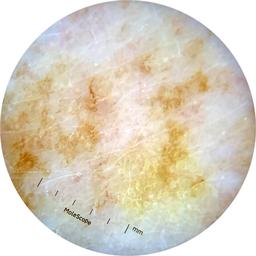

ISIC_9965024

Clinical

Field Value

acquisition_day 129

age_approx 75

anatom_site_1 Head and neck

anatom_site_general head/neck

concomitant_biopsy False

diagnosis_1 Benign

diagnosis_confirm_type single image expert consensus

family_hx_mm False

image_manipulation instrument only

image_type dermoscopic

lesion_id IL_4355888

patient_id IP_7946204

personal_hx_mm True

sex female